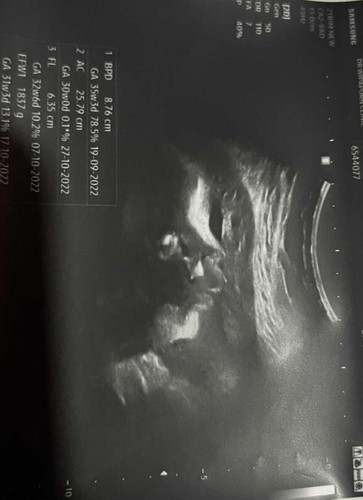

2อาทิตย์ก่อนไปซาวมา หมอถ่ายหน้าน้องได้ชัดเลยค่ะ แต่รู้สึกว่าทำไมปากบนน้องใหญ่จัง แบบนี้เป็นปกติมั้ยค่ะ รบกวนแม่ๆด้วยค่ะ

อายุครรภ์ตอนนี้ 36+3

ปกติค่ะ ซาวดน์ขาวดำจะไม่ชัดเท่าซาวนด์ 3/4มิติ บ้านนี้ซาวนด์จมูกโด่งมากคลอดมาทั้งแหมบทั้งบาน 🤣

ปกติของซาวด์ 2 มิติค่ะแม่ บ้านนี้ตอนซาวด์ 2 มิติก็แปลกๆ แต่พอไปซาวด์ 4 มิติปกติดีค่ะ

2มิติบ้านนี้จมูกเด่นมากส่วนตัวแม่คิดว่ามันใหญ่ไปแต่พอเห็น4มิติเท่านั้นแหละ🥹🥹